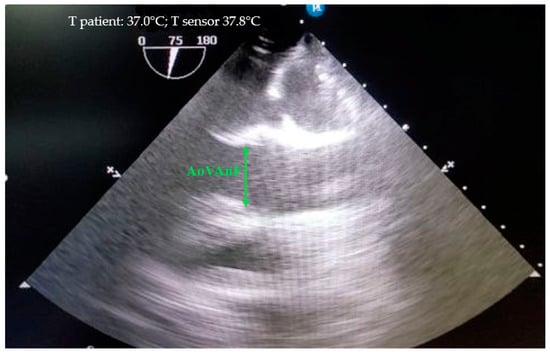

2.4. Ultrasound Study

Echocardiography was performed in accordance with the methods especially designed for animals [17,18] on a Philips CX-50 ultrasound machine (Revision 3.1.2) with an X7-2t transesophageal sensor. The structures of the aortas were evaluated from the fibrous ring of the aortic valve to the ascending part of the aortic arch. The structures of the aorta below were either not visible at all or were difficult to distinguish by echocardiography. Therefore, the size of the aorta below the distal arch was estimated by angiography. The fibrous ring of the aorta was measured at its maximum ring size during systole, with the cursor placed from one inner edge to the inner edge where the flaps attach (Figure 2).

Figure 2. Measurement of the fibrous aortic ring (AoVAnF) in the mini pigs from the “inner edge to the inner edge” at the site of flap attachment, where the ring reaches its maximum size.